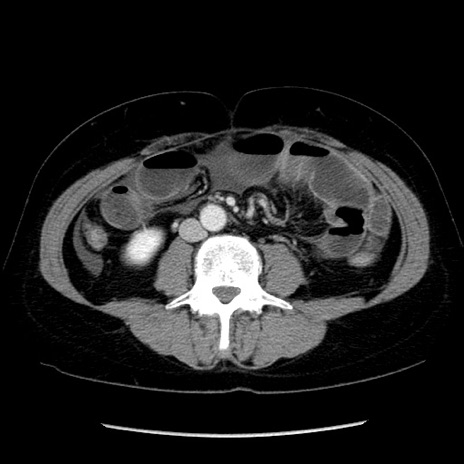

冠状断像

矢状断像